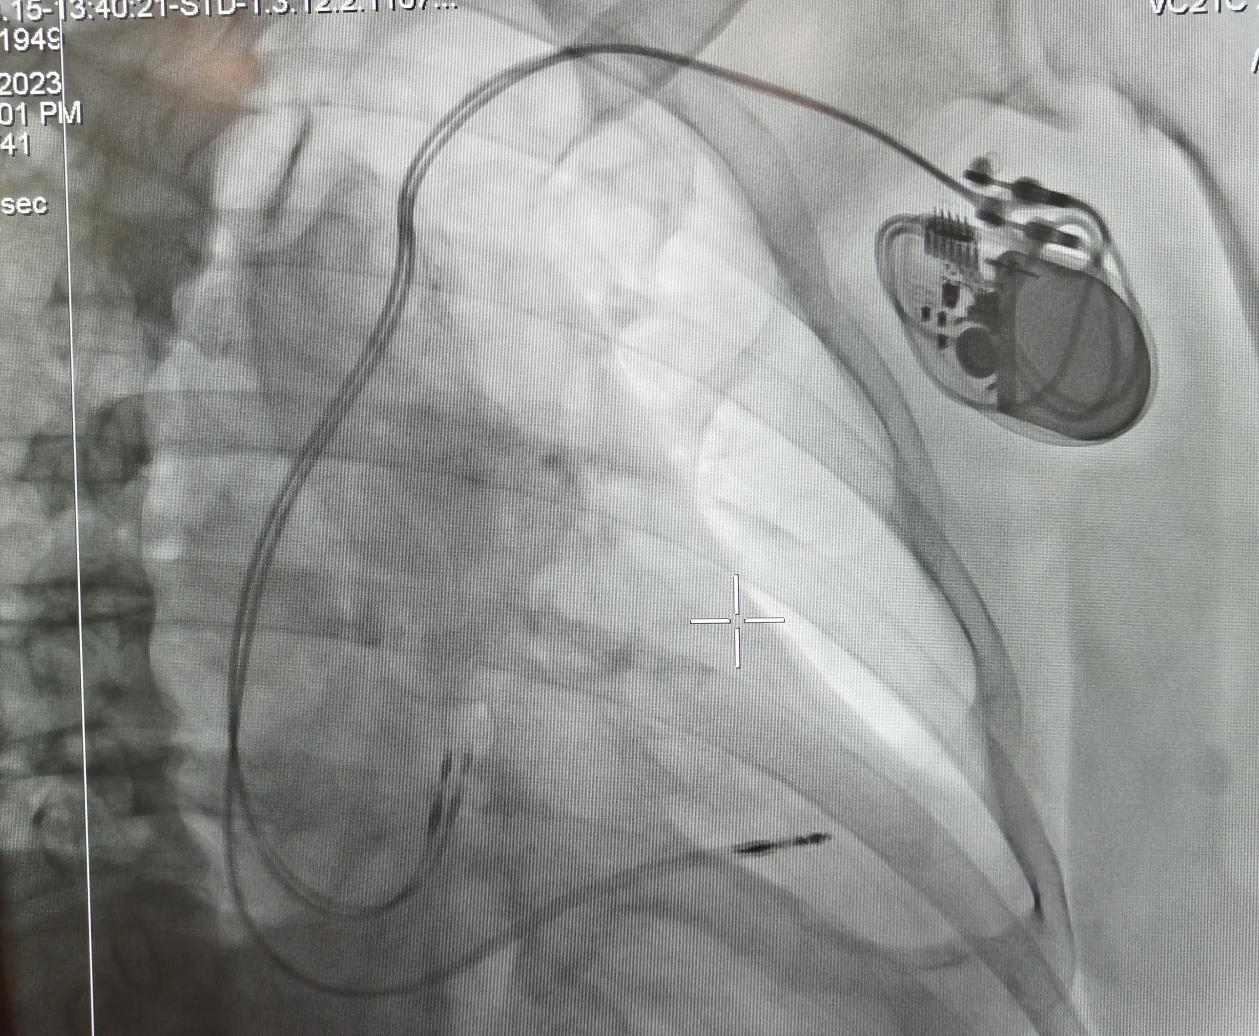

經(jīng)李慧新主任及科室團隊的會診,予以植入永久性起搏器,同時,李主任將患者的基本病情同白中樂教授進行了匯報,術(shù)前白教授詳細詢問患者的情況,為其制定了更精準的治療方案,決定實施永久性起搏器(雙腔)植入術(shù)。8月15日中午,白教授帶領(lǐng)心血管內(nèi)科介入團隊成功為患者實施了“永久性起搏器(雙腔)植入術(shù)”。術(shù)后患者病情平穩(wěn),無頭暈不適。

起搏器植入后影像圖